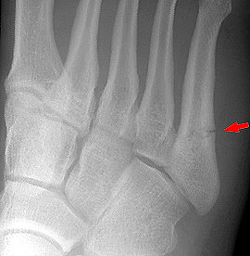

Переломы плюсневых костей

Переломы плюсневых костей по частоте занимают первое место среди всех переломов костей стопы. Обычно возникают при прямом воздействии травмирующей силы (сдавление стопы, падение тяжести или переезд стопы колесом). Могут быть множественными или одиночными. В зависимости от уровня повреждения выделяют переломы головки, шейки и тела плюсневых костей.

Одиночные переломы плюсневых костей очень редко сопровождаются значительным смещение фрагментов, поскольку оставшиеся целыми кости плюсны выполняют функцию естественной шины, удерживая отломки от смещения.

При одиночных переломах плюсневых костей выявляется локальный отек на тыле и подошве, боль при опоре и прощупывании. Множественные переломы плюсневых костей сопровождаются выраженным отеком всей стопы, кровоизлияниями, болью при пальпации. Опора затруднена или невозможна из-за боли. Возможна деформация стопы. Диагноз подтверждается данными рентгенографии в 2-х проекциях, а при переломах основания костей плюсны – в 3-х проекциях.

При переломах костей плюсны без смещения накладывают заднюю гипсовую шину сроком на 3-4 недели. При переломах со смещением проводят закрытое вправление, выполняют открытый остеосинтез или накладывают скелетное вытяжение. Срок фиксации при таких переломах костей стопы удлиняется до 6 недель. Затем пациенту накладывают специальную гипсовую повязку «с каблучком», а в последующем рекомендуют использовать ортопедические вкладки.